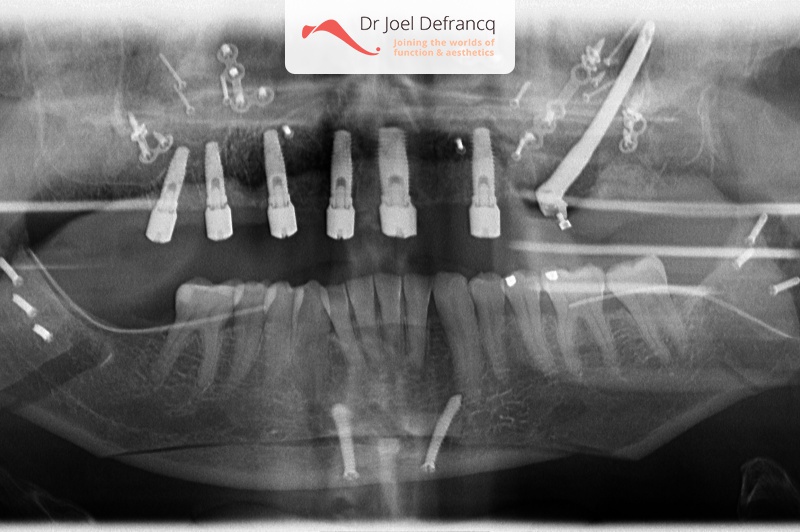

Behandeling tandheelkundige implantaten

- Vaste tanden op implantaten (bovenkaak)